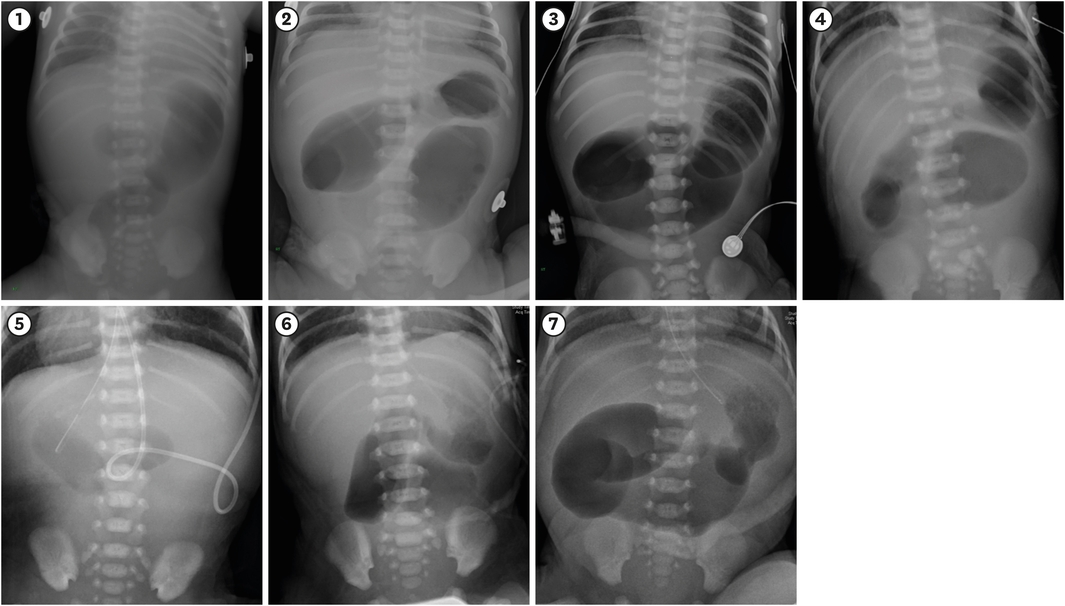

The patients’ characteristics are summarized in Table 1. The sex ratio indicates a male predominance; all patients were prenatally diagnosed with small bowel atresia. All patients were born without critical accompanying malformations, but five patients had associated diseases (Table 1). Only one patient weighed less than 2 kg at birth. Six patients showed a typical triple bubble appearance on the preoperative abdominal film, but this symptom was not observed in one patient (Fig. 1).

Fig. 1

Preoperative abdominal plain radiography. The number in the figure is the number of the individual case. A triple bubble appearance was observed in all cases except case 5.

In diagnosing high jejunal atresia, the triple bubble sign was a reliable finding in this study [15, 16, 19]. The “triple bubble” reflects the air shadows of the stomach, the duodenal bulb, and the proximal jejunum, and it is an excellent indicator of high jejunal atresia. In this study, six of the seven cases had a definite triple bubble appearance on a plain X-ray, although one case lacked this clearly defined triple bubble. In this case, the X-ray may have been taken before full inflation of the proximal atretic bowel. The triple bubble sign is a simple and helpful diagnostic tool for awareness of high jejunal atresia.